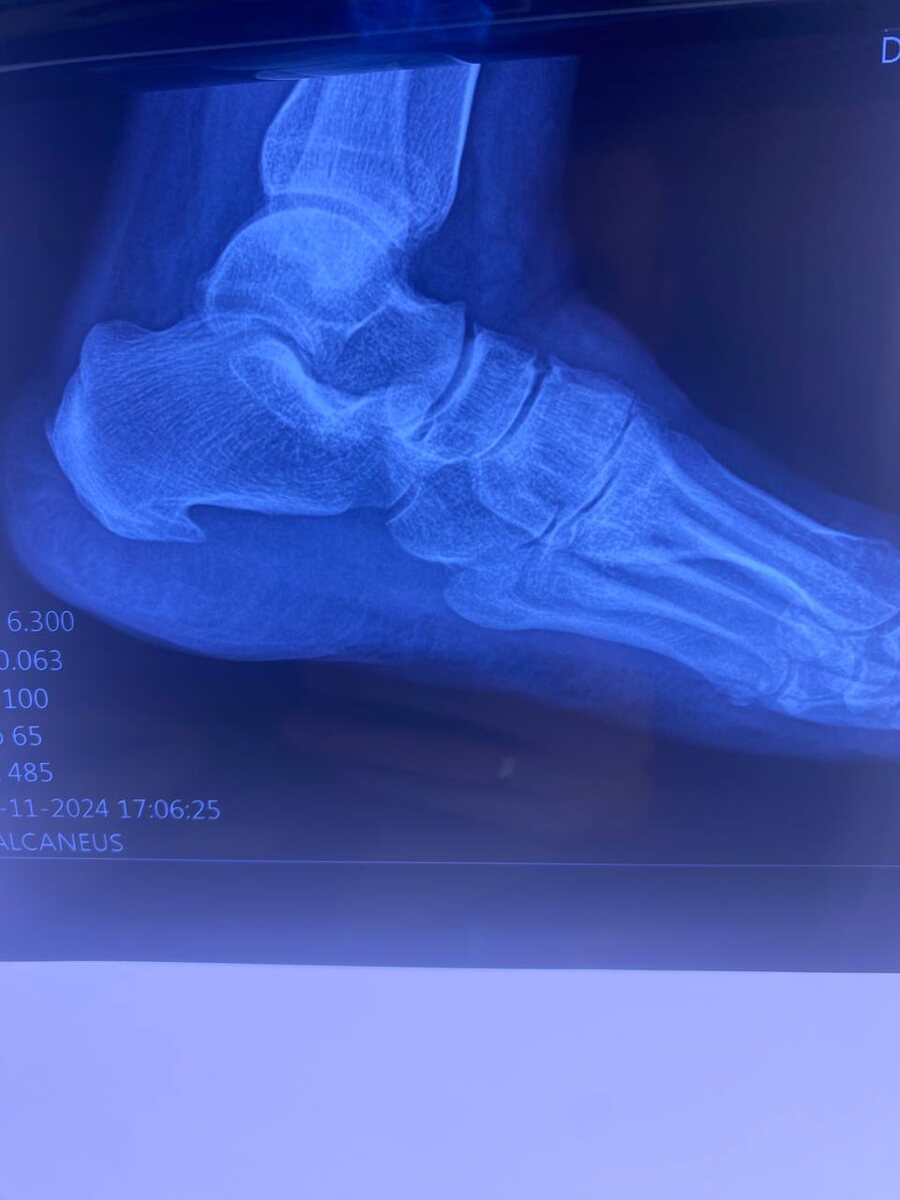

Пяточная шпора – это распространенное заболевание, возникающее в результате воспаления подошвенной фасции. Характеризуется образованием остеофита на пяточной кости, что вызывает сильную боль и дискомфорт при ходьбе. В этой статье мы обсудим симптомы пяточной шпоры, причины, по которым домашние методы лечения могут не помогать, и действительно эффективное решение – ударно-волновую терапию.

Симптомы пяточной шпоры

Основной симптом пяточной шпоры – это сильная и резкая боль в области пятки, которая может усиливаться при:

• Первых шагах после долгого отдыха (например, утром после сна или после длительного сидения).

• Длительной физической нагрузке.

• Хождении по ровной поверхности.

Боль может быть острой или тупой, и часто сопровождается ощущением жжения. Возможно также наличие отека и покраснения в области пятки.